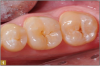

A 0.5 to 1.0 mm layer of Giomer flowable with self-leving properties and low flow was applied to cover the dentin; it was then light-cured for 15 seconds (Figure 8). Uncured resin weakens the restoration at the tooth-restorative interface and may be a pulpal irritant resulting in patient discomfort. It is therefore prudent that the layers closest to dentin be polymerized to their greatest potential. A thin layer of material over the dentin provides the best potential for ultraviolet light-induced polymerization before thicker, harder-to-penetrate layers are added. Sealing the dentin with a thin layer of well-cured Giomer flowable allows ionic release at the restoration-dentin interface. The bond of restorative materials deteriorates with time from many factors, such as enzymes, acids, and mechanical forces, which may decrease sensitivity while increasing restoration longevity. Flowable was then applied to complete the contour of the restoration, and it was then light-cured (Figure 9). The occlusion was checked with articulating paper, adjusted, and polished with a rubber cup (Figure 10). The result was a conservative, esthetic, regenerative restoration.

Fig 9. The tooth was sealed, occlusion was adjusted, and polishing took place.

Figure 9